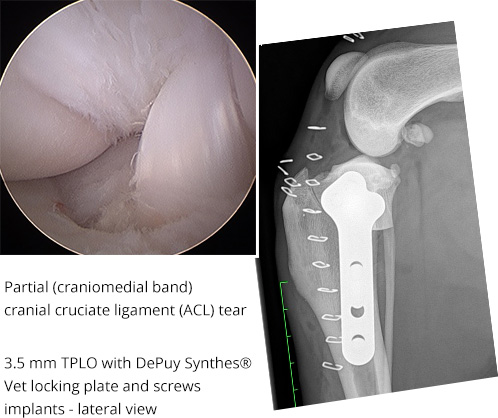

CrCL Tear (TPLO)

This is Matty's knee. Our surgical camera allowed for less invasive surgery and quicker healing.